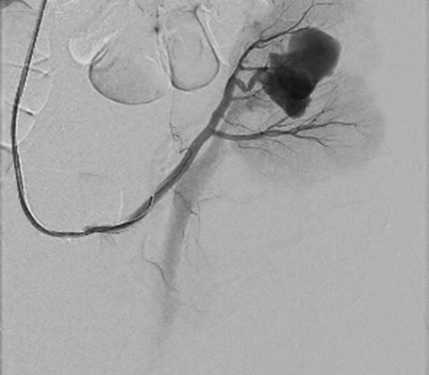

A 52 year old woman arrived at a hospital for a routine health check-up. Abdominal ultrasound revealed a 4.5 cm diameter lesion in the right kidney. Patient was directed to perform a contrast-enhanced computed tomography (CT), which was performed to specify the nature of the formation. CT found 49 mm x 34 mm cyst in the middle-lower portion of right kidney with septum and contrast accumulation (Figure 1), it was classified as Bosniak III and partial nephrectomy was chosen as a main choice of treatment.

Figure 1. A contrast-enhanced Computed Tomography of abdomen was performed (a 49 mm x 34 mm cyst in the middle-lower portion of right kidney with septum and contrast accumulation was found (white arrow)